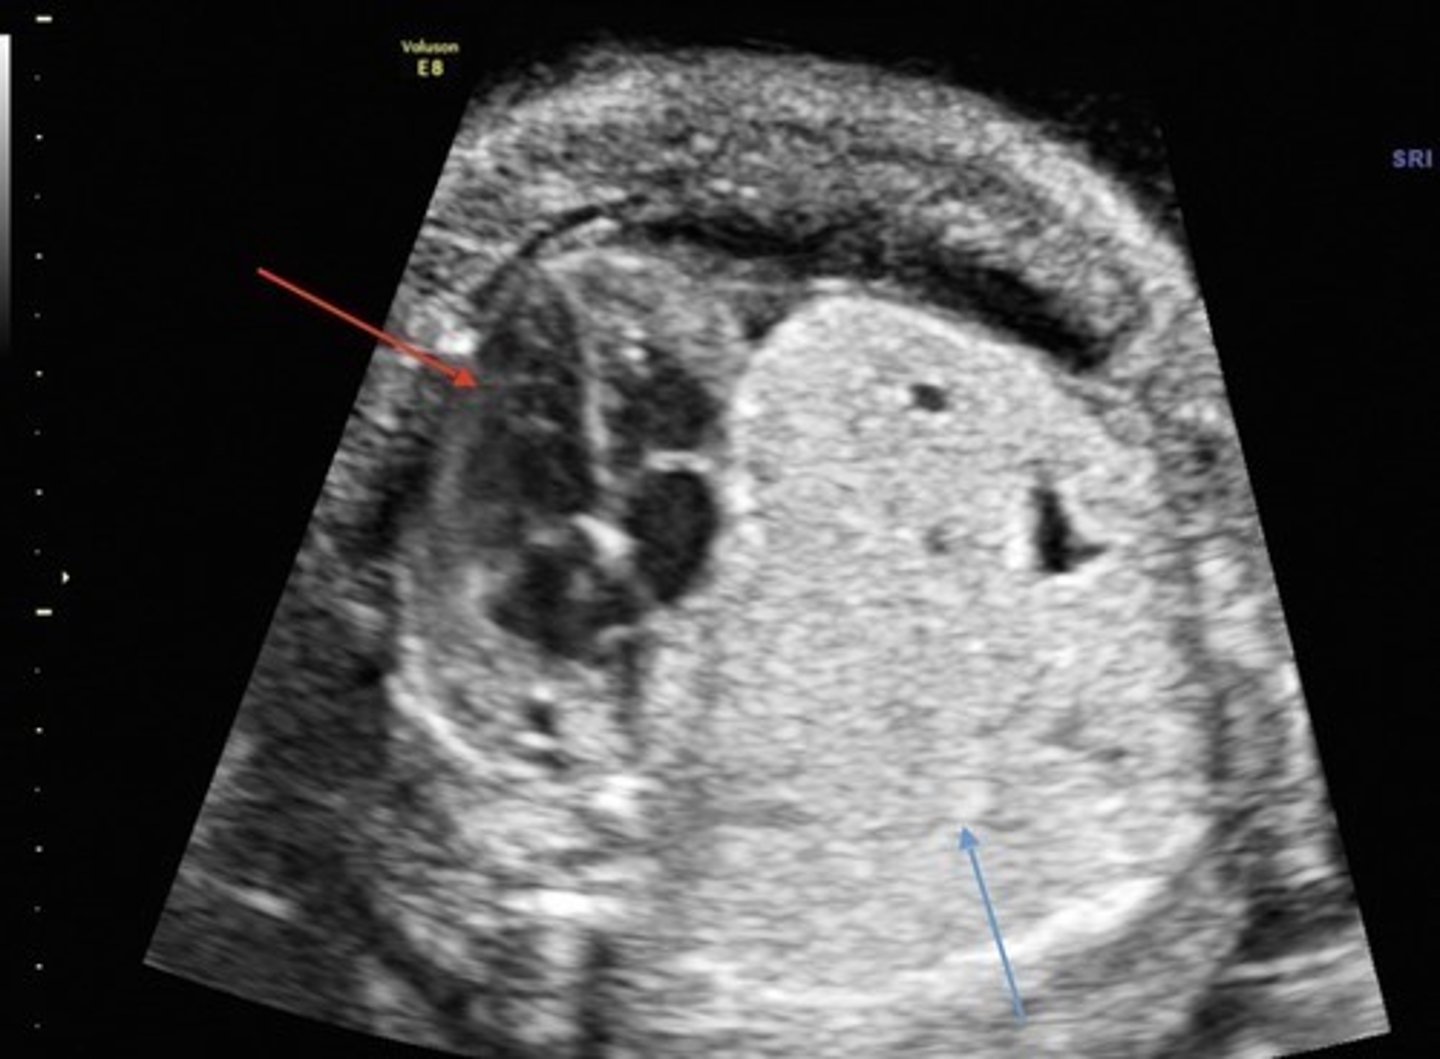

Diaphragmatic Hernia

Herniation of abdominal organs into thoracic cavity through defect in diaphragm